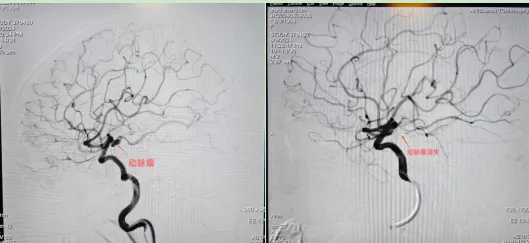

在取得赵女士家属的理解和信任后,紧急开通绿色通道,立即行脑血管造影+颅内动脉瘤介入栓塞术。术中造影再次证实,该患者右侧颈内动脉后交通动脉段血管壁可见不规则突起,大小约4.22mm×5.8mm瘤颈3.2mm,瘤体顶端血管壁向外有突起,考虑为责任动脉瘤,且患者为胚胎型大脑后动脉,一旦手术不当,可能影响血流速度,导致并发症。

三维显示动脉瘤形态

由于该动脉瘤随时可能再次破裂危及生命,王磊及科室医生立即为赵女士在全麻下行动脉瘤栓塞术,历经6小时,手术顺利结束,术后造影见动脉瘤不显影,载瘤动脉通畅。该手术的成功也标志着我院在急诊治疗破裂动脉瘤方面,正在与时俱进,跨上了一个新台阶。